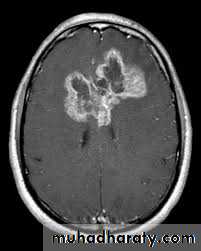

Meningioma

Benign tumor arise from the arachnid cells of the meningeal covering of the brain are most common primary intracranial neoplasm

Usually present in middle age female

it is well defined extra axial , located mainly at the convexity of the skull periphery

CT finding

meningioma presented as isodense area or slightly hyper density area with surrounded crescent of hypo density ( csf cap ) post contrast injection the lesion enhance homogeneously with enhancing Dural tail .

20 % show calcification

hyperostosis & thickening of the near by bony part of the skull & diplioc space .

it may be associated with little or no peri focal edema .

if the lesion associated with central necrosis with large perifocal edema meningio sarcoma should be excluded .